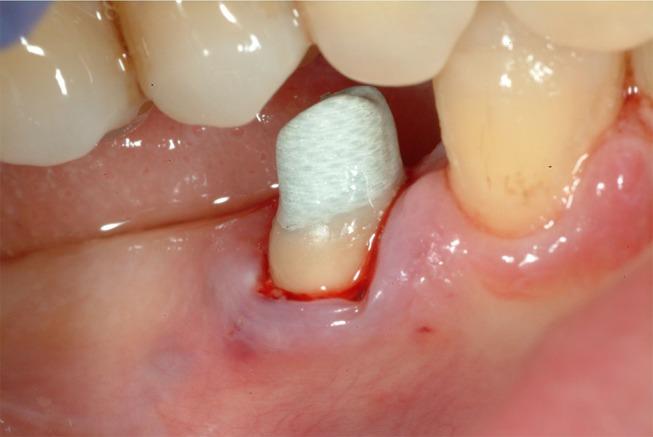

In the reported case an intraoral scan was used to mill a post and core restoration on an endodontically treated inferior premolar; this operative protocol was based on previous in vitro experiments that confirmed the ability of 3shape Trios scanner to read post-space up to 9 mm in depth.

The digital technique allows us to convert the concave surface of the root canal into the convex surface of the post, and realize an anatomical post and core that improves the biomechanics of the endodontically treated tooth reducing the possibility of root fractures.

在本报告病例中,使用口内扫描仪为一颗根管治疗后的下颌前磨牙制作桩核修复体;该手术方案基于先前的体外实验,该实验证实了3shape Trios扫描仪能够读取深度达9毫米的桩道空间。

数字技术使我们能够将根管的凹面转化为桩的凸面,并制作出解剖形态的桩核,改善根管治疗后牙齿的生物力学性能,降低牙根折断的可能性。